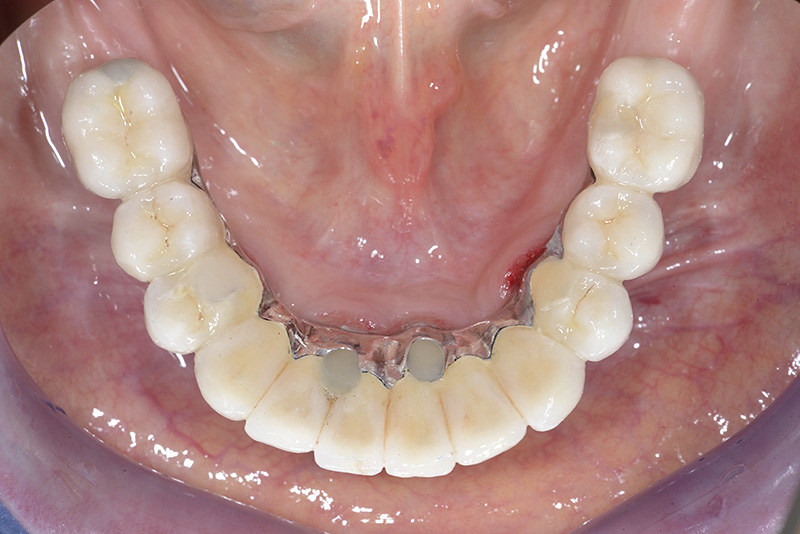

PREMESSA: in seguito all’estrazione dell’incisivo laterale superiore di destra, resasi necessaria per cause batteriche, si decide di affrontare il caso con il posizionamento di un impianto in sostituzione dell’elemento mancante dopo guarigione del sito infetto. Con tecniche rigenerative sia dei tessuti ossei mancanti a causa dell’infezione pregressa, sia dei tessuti gengivali che appaiono inizialmente troppo spostati in alto, si ripristina una corretta morfologia delle parabole (contorni) gengivali e delle papille interdentali (triangoli di gengiva tra due denti vicini).

Vengono utilizzati 2 tipi di provvisori: il primo, cementato ai denti vicini, viene utilizzato dal momento dell’estrazione del dente fino ad impianto osteointegrato (circa 6 mesi); il secondo, avvitato direttamente all’impianto, ha una funzione di prova estetica ma soprattutto di guida per la maturazione dei tessuti gengivali peri-implantari portandoli verso la maturazione completa prima di posizionare la corona finale in disilicato di litio.